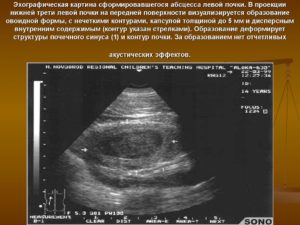

Объемное образование почки: что это, виды и лечение